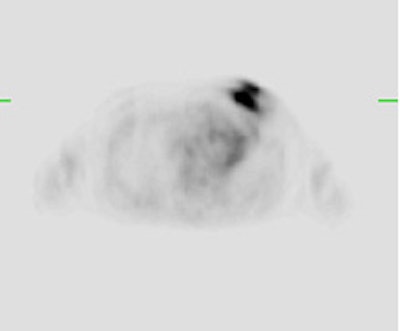

Monitoring response to therapy: The patient shown below had received chemotherapy for treatment of metastatic breast cancer (pre-therapy scan is on the left). The post-therapy scan (right image) demonstrated a very good response to treatment, however, several foci of tracer uptake remained (black arrows) consistent with residual metastatic disease. Further therapy was planned as a result of the PET scan. |

|